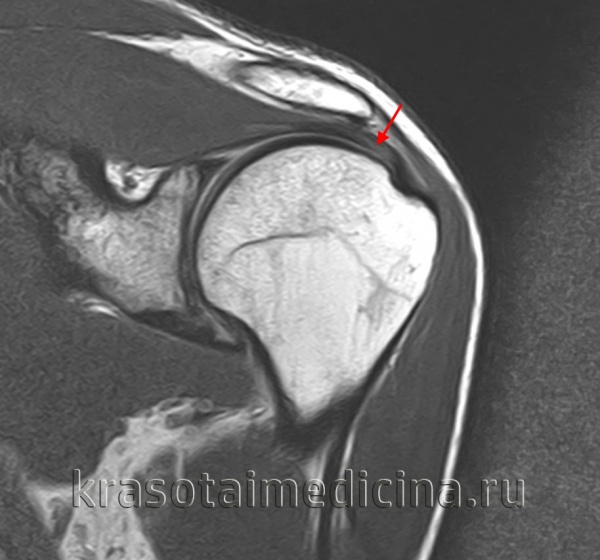

Диагноз повреждения ахиллова сухожилия выставляется на основании клинических данных, при необходимости может использоваться МРТ. В первые двое суток при незначительном расхождении концов сухожилия возможно консервативное лечение. На конечность накладывают гипс в положении максимального подошвенного сгибания сроком на 6 недель. При застарелых повреждениях и неудаче консервативной терапии показана операция.

Для уточнения диагноза используется сравнительная рентгенография коленных суставов (надколенник с больной стороны смещен кверху), МРТ коленного сустава и УЗИ сустава. Лечение оперативное, осуществляется в стационарных условиях. Колено разгибают, концы связки сближают и соединяют при помощи матрацных швов. При отрыве костной пластинки накладывают трансоссальные швы. Иммобилизацию продолжают 2-3 недели. После операции назначают антибиотики и анальгетики, в последующем – ЛФК, ультразвук, диадинамические токи, парафин и массаж.

Диагноз уточняют при помощи УЗИ или МРТ. При неполных разрывах накладывают гипс на 3-6 недель, затем назначают ЛФК. При полных разрывах сухожилие сшивают в условиях стационара. При свежих повреждениях применяют матрацные швы, при застарелых разрывах производят удлинение сухожилия с использованием лоскута из четырехглавой мышцы. Послеоперационную иммобилизацию осуществляют в течение 6 недель, в реабилитационном периоде назначают озокерит, парафин, ультразвук, массаж и ЛФК.